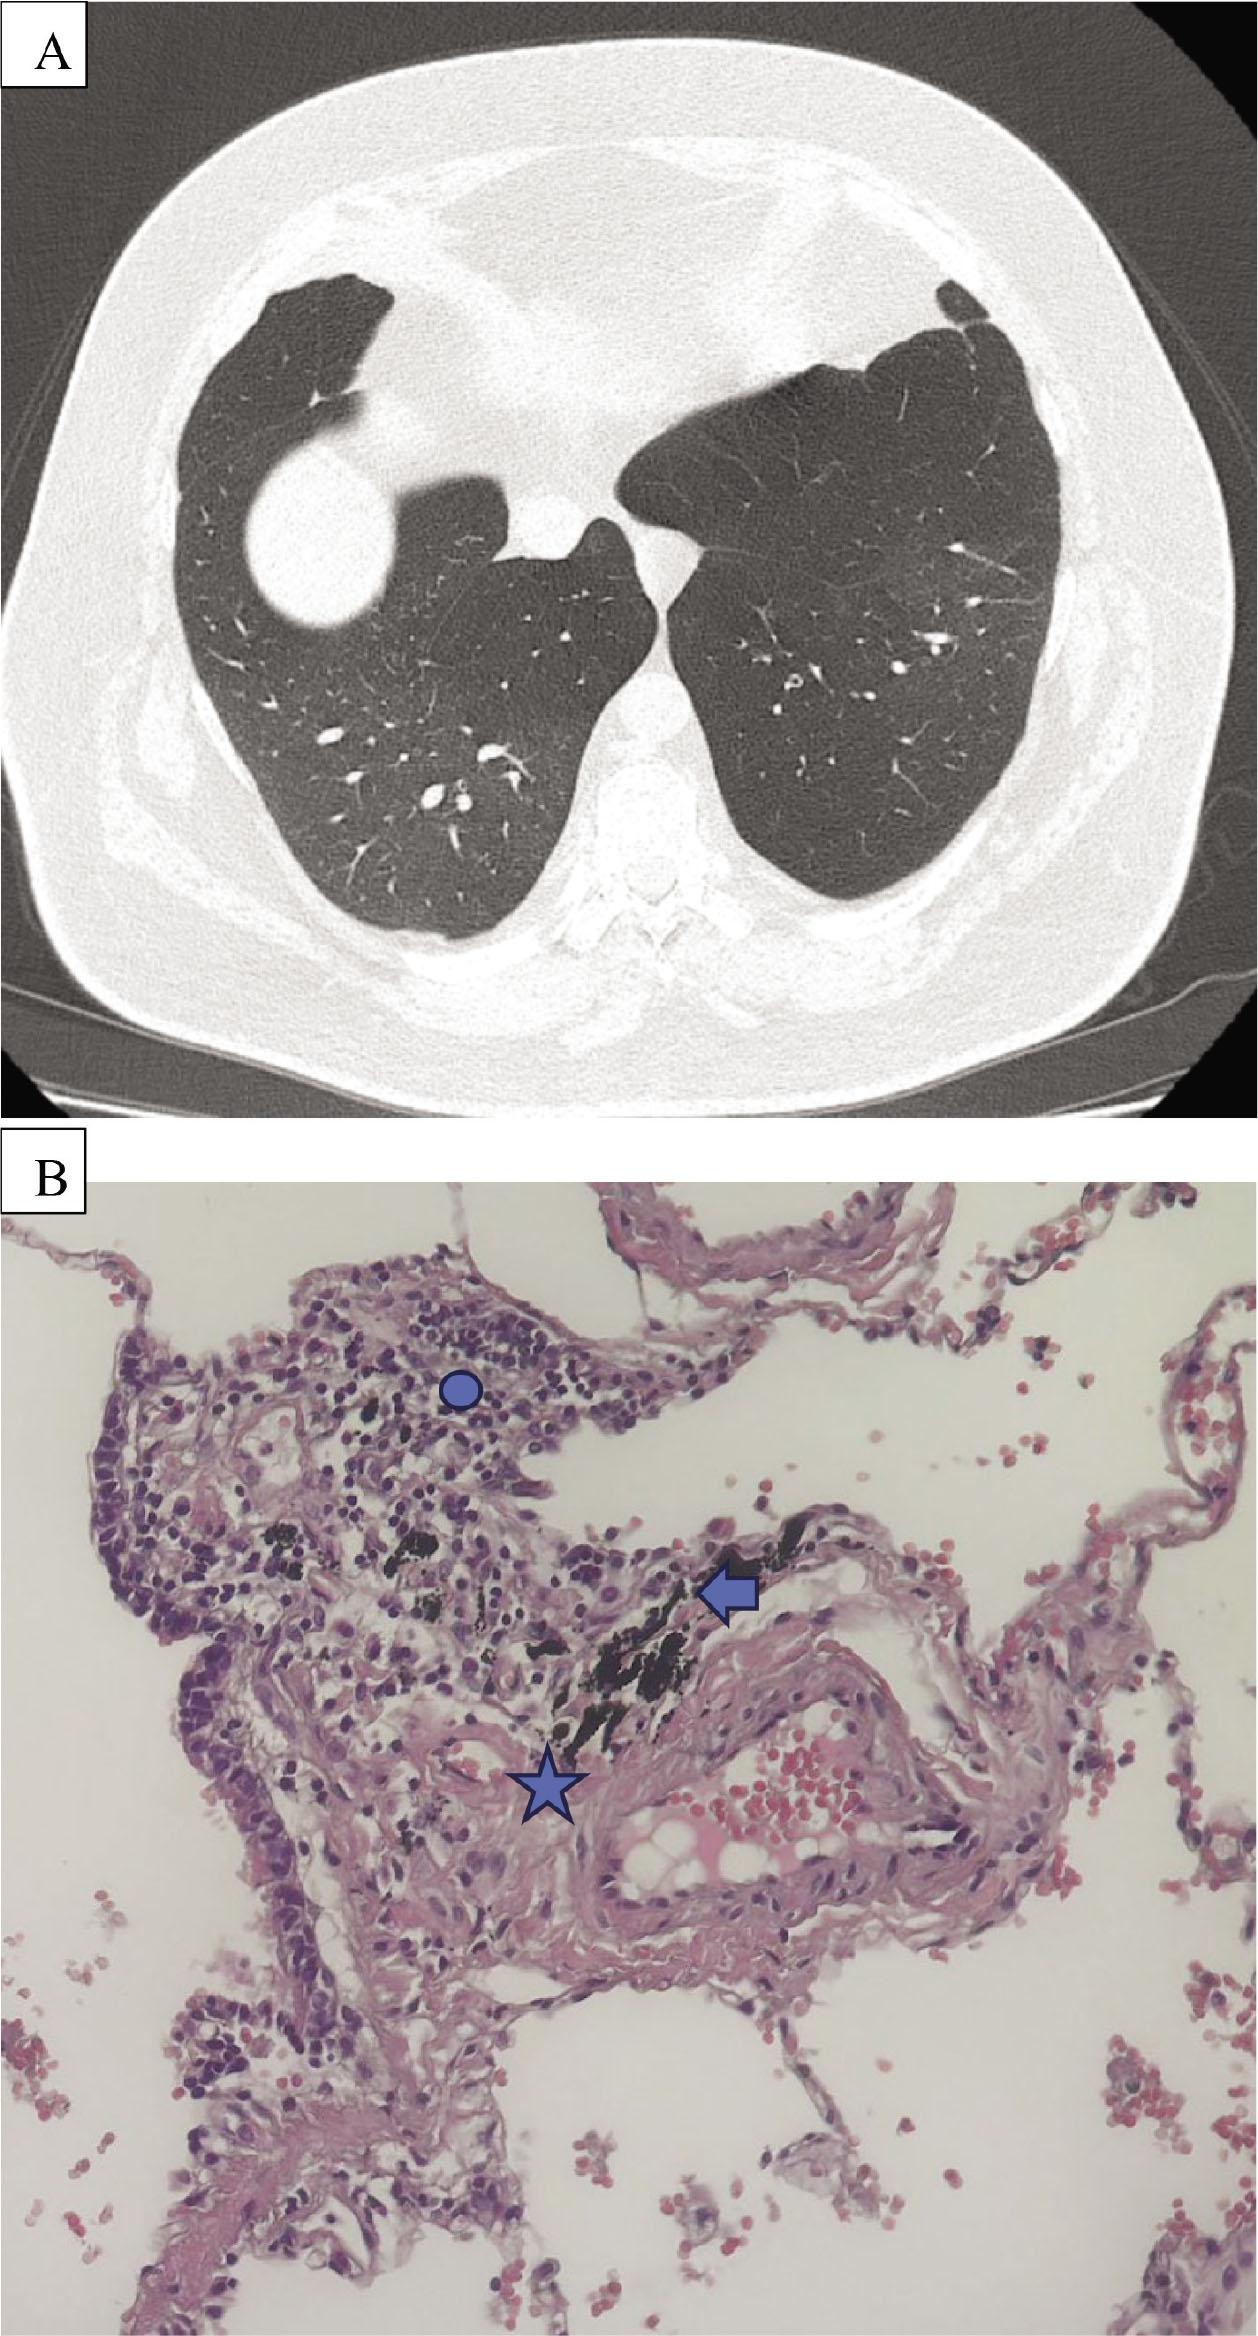

Figure 3A.

| Lung Biopsy | No | No | Yes |